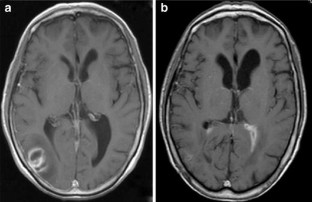

We performed an iMRI-guided surgical procedure in a patient with a cystic lesion of the inferior parieto-occipital lobe while the patient was placed in a semi-sitting position, employing a mobile 0.15-T intraoperative MRI system. For that purpose, we adapted a standard OR table according to the needs of iMRI.

Patient positioning could be accomplished easily. For intraoperative scanning, the OR table was tilted backwards so as to position the patient’s head in the magnet’s aperture. Obtained images were used for neuronavigated cyst evacuation via burr hole trephination after repositioning the OR table. Subsequent intraoperative imaging documented collapse of the cyst at the end of the procedure. There were no adverse effects resulting from the combination of semi-sitting position and iMRI guidance.